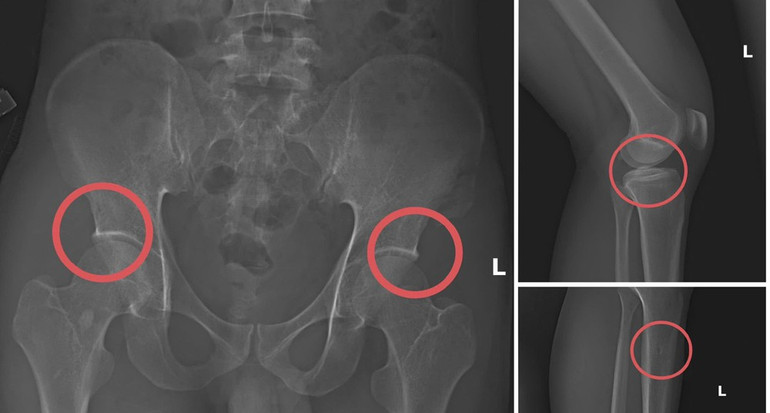

| Bản phim chụp XQ một số tổn thương xương do đối tượng tạo ra nhằm trục lợi tiền bảo hiểm nhân thọ. Ảnh: Công an cung cấp |

Sau khi nạn nhân được tiêm thuốc mê, Châu dùng kim và búa gây nứt hoặc vỡ xương theo đúng vị trí dễ được chi trả cao. Khi thương tích hình thành, cả nhóm tiếp tục dựng bối cảnh như ngã suối, điện giật hoặc trượt ngã để hợp thức hóa hồ sơ bệnh án.

Tri thức y khoa vốn giúp bệnh nhân tránh thương tổn, phục hồi vận động và tìm lại sự ổn định trong cơ thể. Vậy mà trong vụ việc này, kiến thức ấy lại tham gia vào quá trình lựa chọn vị trí dễ gây nứt, kiểu gãy nào tạo được tấm phim X quang phù hợp, cách tác động lực ra sao để thương tích giống tai nạn nhất. Những thao tác từng gắn với mục tiêu chữa trị nay được lồng vào một kế hoạch tính toán tinh vi, khiến người quan sát khó tránh khỏi cảm giác trĩu nặng.